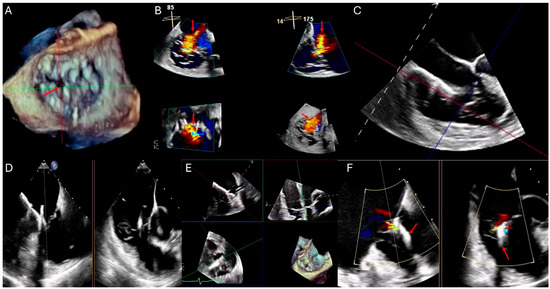

| Transesophageal Echocardiography (TEE) | Enhanced visualization of the tricuspid valve in cases with poor TTE windows. Useful for assessing leaflet morphology, tricuspid annulus, chordae tendineae, and device-related TR, particularly in patients with cardiac implantable electronic devices (CIEDs) [22,23]. | Superior resolution of valve anatomy and leaflet morphology compared to TTE. Useful for guiding interventions such as transcatheter tricuspid valve repair or replacement. Allows better visualization of prosthetic valve function [22,23]. | Semi-invasive procedure requiring sedation. Limited field of view for evaluating right ventricular function and dependent on transducer positioning for optimal imaging. Potential for esophageal injury or discomfort [22,23]. |